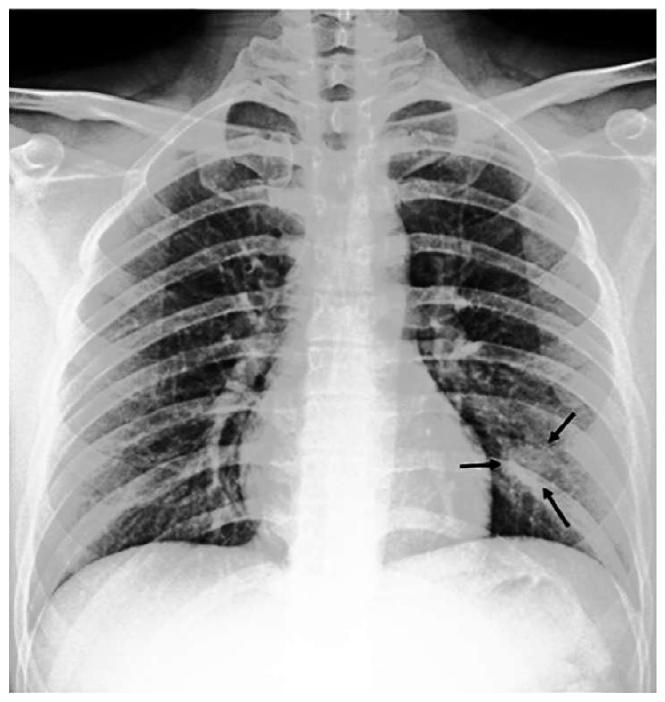

The most common imaging technique used as the first clinical step for chest-related diseases is CXR [26]. Hence, more CXRs could be collected publicly than CT images. A batch of randomly selected samples from the dataset with frontal view, also known as anteroposterior (AP) or posteroanterior (PA), is shown in Fig. 1.

Figure 1: Randomly selected frontal CXR images from different sources